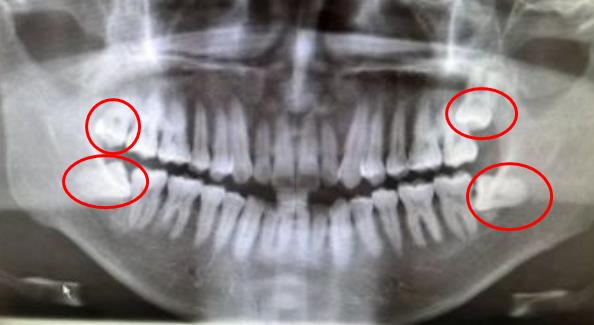

正常情況下,目前很少有4顆智齒生長出來了,且位置很正,沒有長歪的情況。大部分智齒都是萌出一點點,或者是完全沒有萌出,埋伏在牙槽骨內(nei) ,這種阻生智齒是需要拔除的,部分智齒可能暫時沒有產(chan) 生危害,但是長期下來可能會(hui) 造成周圍組織腫脹疼痛甚至是鄰牙齲壞等情況。所以從(cong) 長遠意義(yi) 上來說,位置不正的智齒是建議全部拔除的。